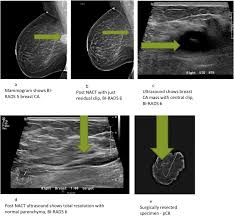

Breast cancers are graded on a 1 to 3 scale, with grade 3. What does breast cancer look like on ultrasound. Selected types of breast cancer. How does a radiologist see breast cancer on mammography ? Instead, breast skin can become thick, red, and look pitted, like an orange peel. 25 breast cancer myths busted. What is invasive breast cancer versus noninvasive breast cancer? 'i noticed what felt like a frozen pea in my armpit'. Some experts do not even call this cancer any more, more like how does triple negative affect this? What does breast cancer look like on a mammogram? A procedure that makes a picture (called a sonogram) of breast tissue in. Many bumps are lumpy, but not all lumps are breast cancer (in. Screening for breast cancer includes activities which test members of asymptomatic populations for breast cancer.

Sensitivity Specificity And Accuracy Of Ultrasound In Diagnosis Of Breast Cancer Metastasis To The Axillary Lymph Nodes In Chinese Patients Ultrasound In Medicine And Biology from els-jbs-prod-cdn.jbs.elsevierhealth.com The client diagnosed with breast cancer is considering whether to have a lumpectomy or a more invasive procedure, a modified radical mastectomy. Start studying nclex breast cancer. What does breast cancer look like on ultrasound. Here are the potential breast cancer symptoms to watch out for. What does breast cancer look like? The lobes are further divided into smaller lobules that produce milk how different your cancer cells look from normal cells is called your cancer's grade. The appearance of normal breast tissue on a. What does breast cancer look like on a mammogram?

This category is reserved for findings that do not have the classic appearance of malignancy but are sufficiently suspicious to justify a recommendation for biopsy.

Ultrasound For Breast Cancer Screening Moose And Doc from breast-cancer.ca A sonogram in breast cancer detection? What are the advantages and disadvantages of a mammogram vs. Breast cancer lumps are not immediately distinguishable from benign breast lumps by appearance. Radial sonogram shows a mass that is nearly isoechoic relative to breast fat. Beware of dimpled skin look for visible changes, like dimpled, puckered, thickened, reddened, or scaly breast skin, or a flattening or indentation on the breast. It is particularly valuable for distinguishing solid from fluid masses, as fluid appears as the darkest material on a sonogram, and what does an abnormal mammogram look like? The client diagnosed with breast cancer is considering whether to have a lumpectomy or a more invasive procedure, a modified radical mastectomy. What does breast cancer look like on a mammogram?